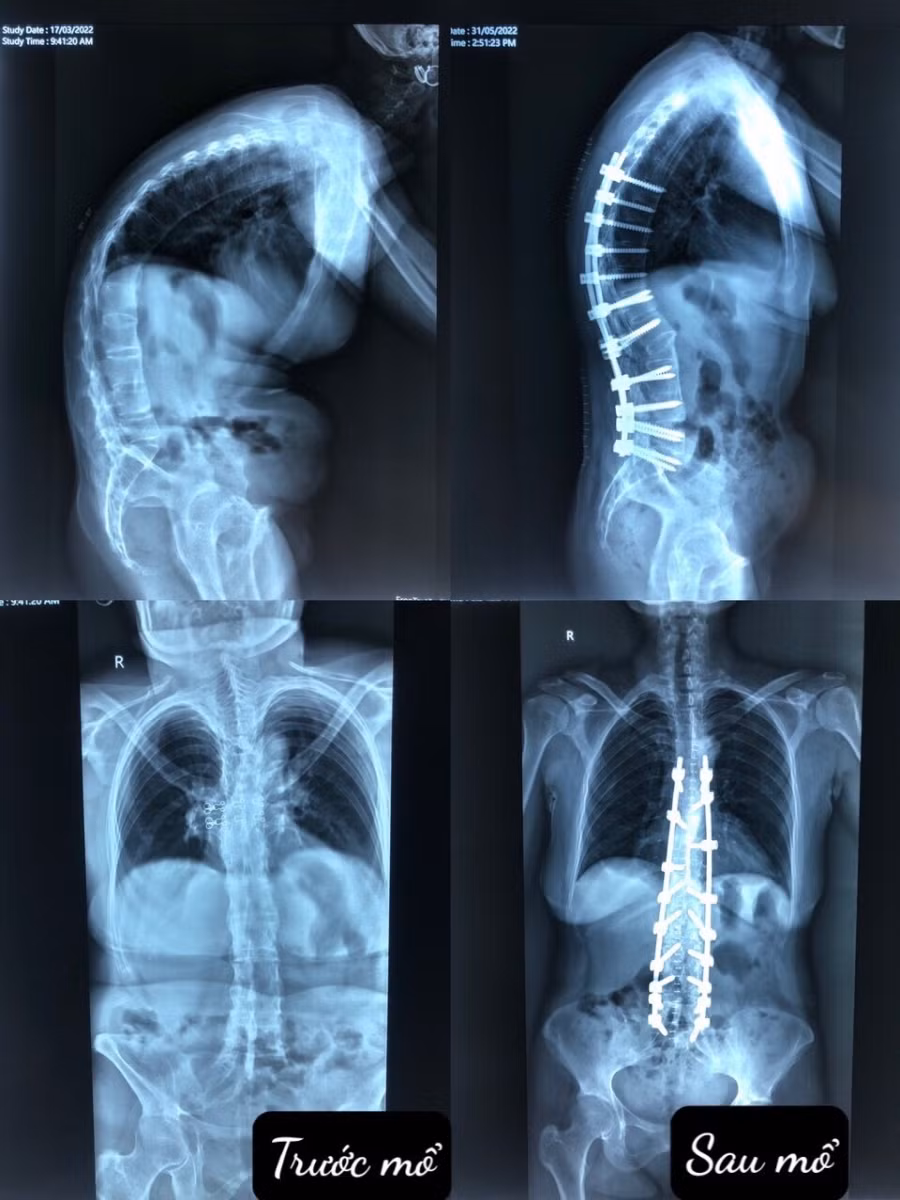

Bệnh mỗi lúc một tiến triển nặng làm lưng chị gù xuống, tầm nhìn hạn hẹp, không thể nhìn thẳng như những người bình thường, thân hình ngày càng biến dạng, ảnh hưởng đến sức khoẻ và tinh thần.

Chứng kiến nỗi đau của vợ mình, anh chồng quyết tâm chạy chữa tìm mọi giải pháp để giúp vợ. Sau khi thăm khám tại nhiều bệnh viện, các bác sỹ đều xác định Gù do viêm cột sống dính khớp là 1 bệnh lý chỉnh hình cột sống không hề đơn giản, nếu phẫu thuật thì có thể gặp phải rủi ro tai biến và kỹ thuật này chỉ có những bệnh viện lớn, chuyên môn cao mới thực hiện được.

Trong suốt 5 giờ đồng hồ cân não, các bác sỹ dành hết sự tập trung cao độ, chú ý từng chi tiết nhỏ nhất. dao mổ cầm và trao tay cũng phải cẩn thận, chỉ khâu cũng tương tự. Ca mổ diễn ra thuận lợi, bệnh nhân được phẫu thuật cắt 2 vạt xương, cố định cột sống, nắn chỉnh gủ.

Sau mổ, bệnh nhân tỉnh táo và có thể nằm ngửa sau hơn 10 năm phải nằm nghiêng sang 2 bên. Ba ngày sau, chị đã đi lại được bình thường, lưng đã thẳng, tầm nhìn không còn hạn chế, ngoại hình thay đổi một cách ngoạn mục.